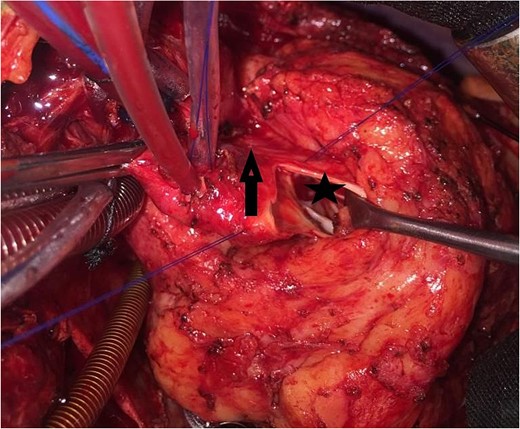

An 11-year-old girl was referred to our hospital with a main complaint of progressive exertional dyspnea. She had undergone surgical repair of SAS 6 years ago. Transthoracic echocardiogram (TTE) revealed the following findings: severe left ventricular hypertrophy, tunnel-like fibromembranous subaortic stenosis with a length of 10 mm, a peak gradient (PG) across the LVOT of 170 mmHg, and mild aortic regurgitation. Based on these findings, the patient was scheduled for elective surgical repair with a possible indication for MKO. The operation was performed via median sternotomy with great caution to avoid inadvertent rupture of any cardiac cavity due to heavy adhesions from the previous operation. The aorta was cannulated just below the takeoff of the innominate artery. Bicaval cannulation was performed to provide a bloodless field. Aortic cross-clamping was applied, and antegrade cold blood cardioplegic solution was administered via a catheter placed in the ascending aorta. The ascending aorta was opened transversely 1 cm above the sinotubular junction (Fig. 1). The aortic valve leaflets were examined carefully to confirm that the aortic valve could be preserved. LVOT was examined thoroughly, and it was clear that the stenosis in the subaortic area was so complex that simple resection through the aortic valve orifice would not be sufficient. The right ventricular outflow tract was opened transversely below the pulmonary valve. The conal papillary muscle was identified (Fig. 2). A right-angle instrument was introduced through the aortic orifice into the interventricular septum, and the tip of the instrument was used to perforate the conal septum to the left of the conal papillary muscle to prevent damage to the conduction system; the septal incision was completed with great caution to avoid damage to the aortic cusps and to extend the incision downward as necessary to completely relieve the stenotic subaortic area (Fig. 3). Interrupted 5/0 Prolene sutures were placed circumferentially around the septal incision to close the interventricular septal defect using a bovine pericardial patch to provide adequate widening of LVOT (Fig. 4). The right ventriculotomy was closed with a second bovine pericardial patch to avoid any possible obstruction of the right ventricular outflow tract (Fig. 5). The remainder of the operation was completed uneventfully. After 6 hours of mechanical ventilation, the patient was extubated, and she convalesced well postoperatively. TTE showed excellent results of the operation with PG across LVOT of 20 mmHg. On 1 year follow-up, the patient was asymptomatic and in very good general condition, and TTE findings confirmed the excellent result.

Intraoperative image showing the interrupted sutures placed around the septal incision.